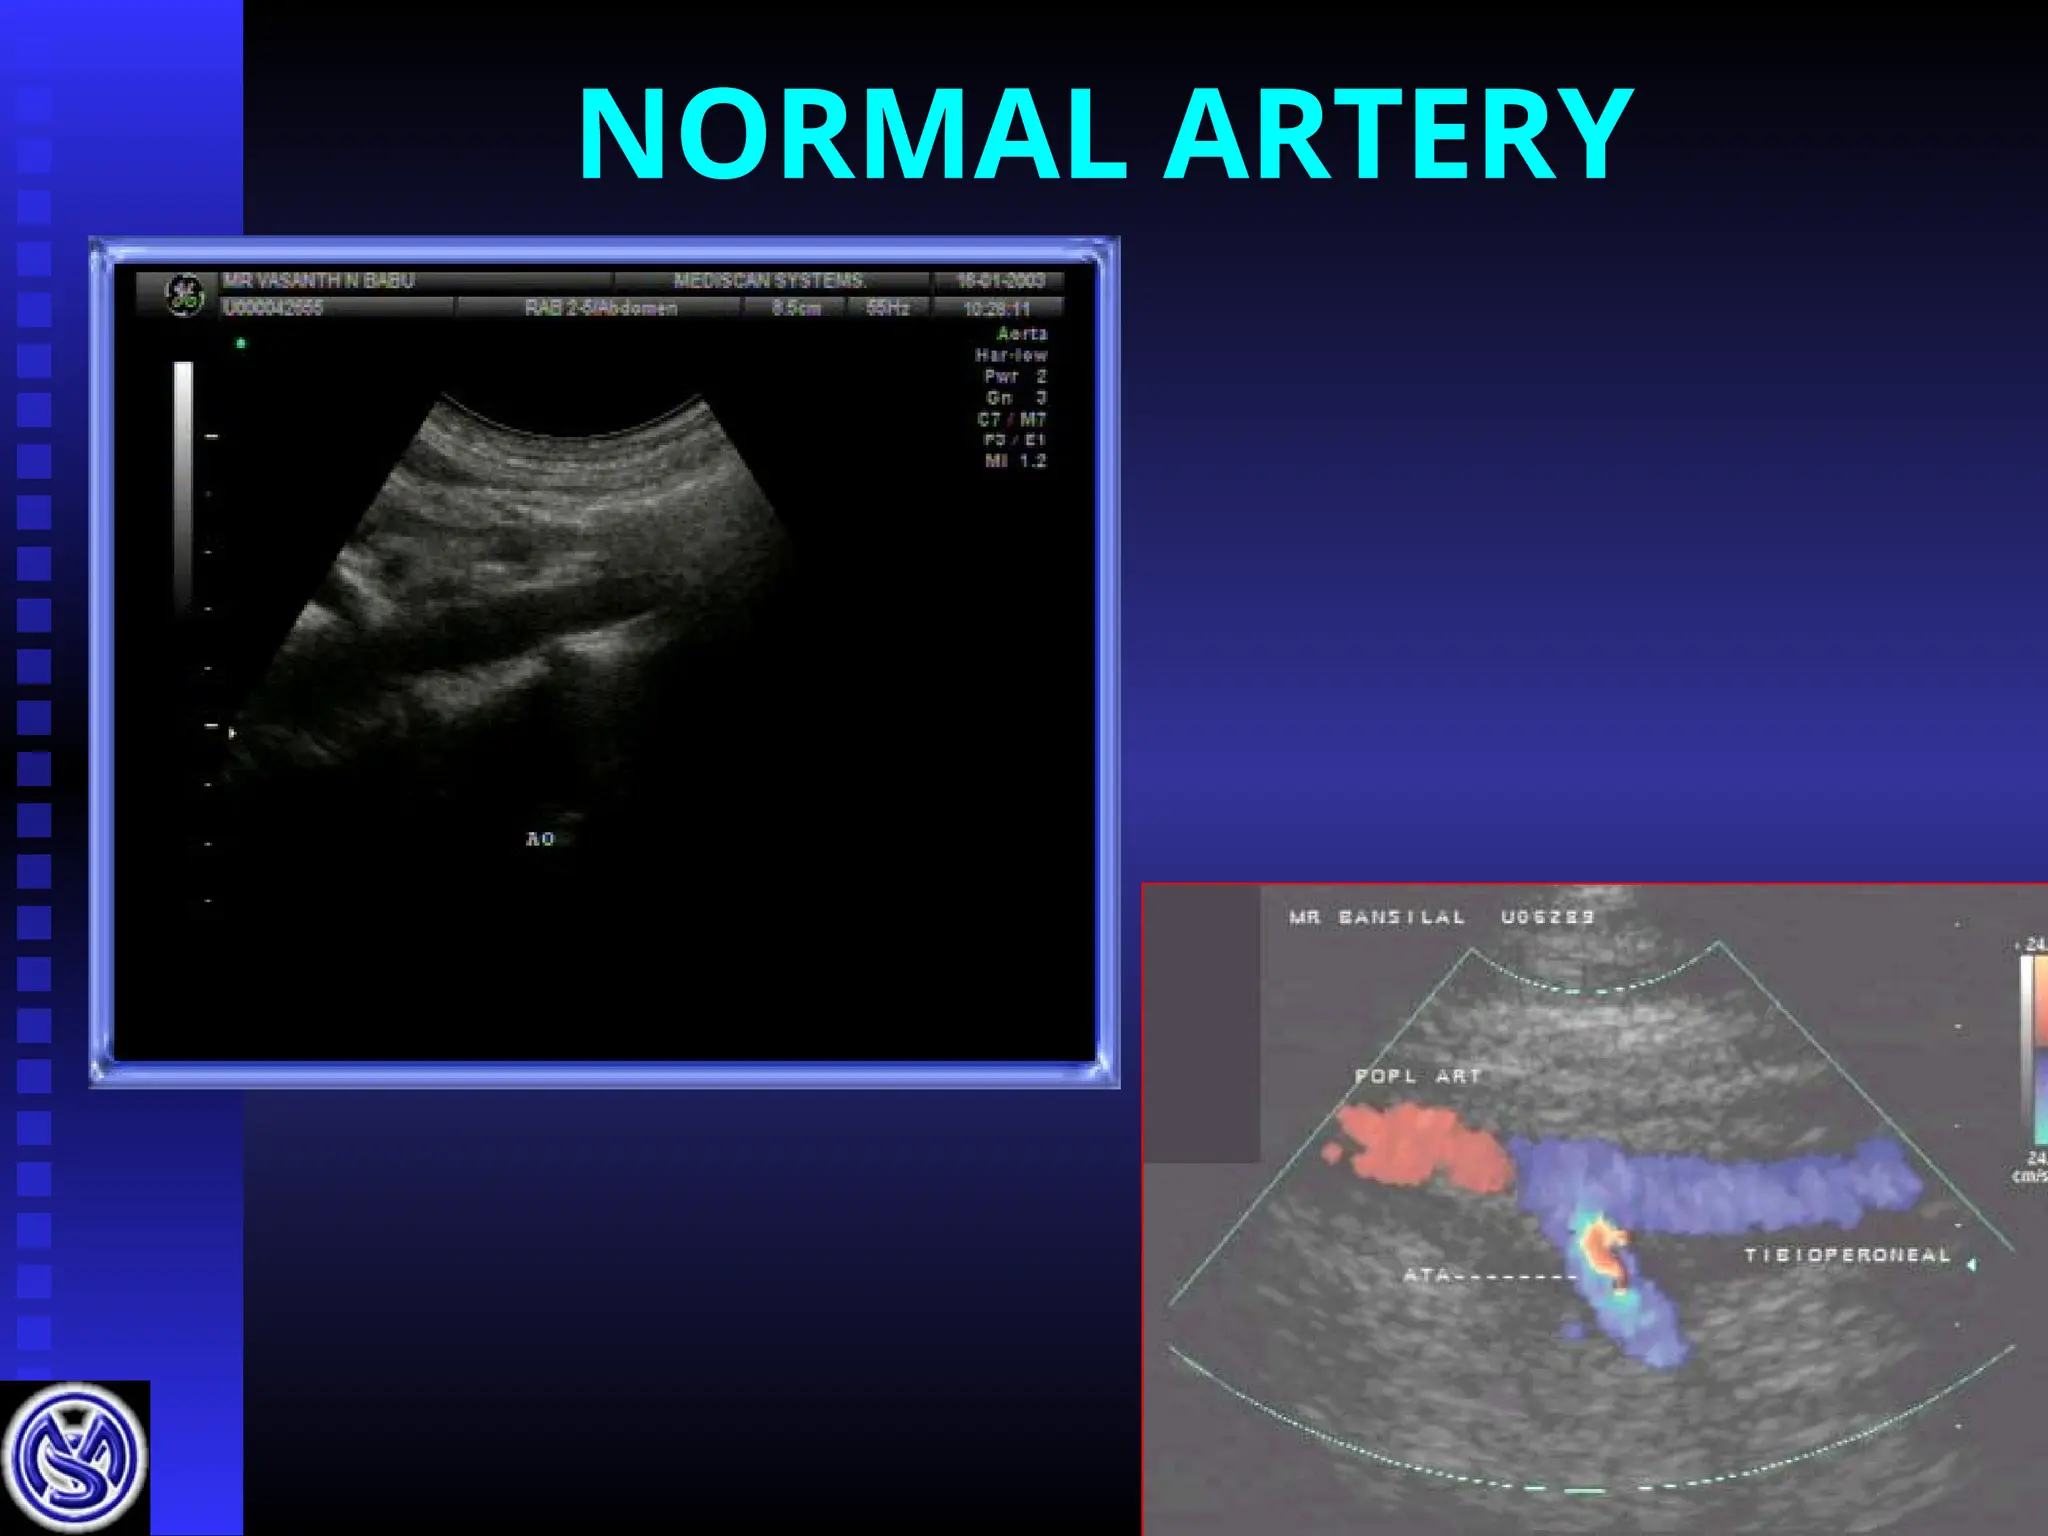

NORMAL ARTERY

Normal arterial waveform

Mean arterial diameters and

peak systolic velocities

Artery

Artery Diameter

Diameter

(mm)

Velocity

cms/sec

Ext.iliac

Ext.iliac 7.9

7.9 +

+ 1.3

1.3 120

120 +

+ 20

20

Common

Femoral

8.2

8.2 +

+ 1.4

1.4 115

115 +

+ 25

25

Sup. Fem A

Sup. Fem A 6.0 + 1.2

6.0 + 1.2 90

90 +

+ 13

13

Sup Fem A

distal

5.4 + 1.1

5.4 + 1.1 93.6 + 14.1

93.6 + 14.1

Popliteal

Popliteal 5.2 + 1.1

5.2 + 1.1 68.8 + 13.5

68.8 + 13.5